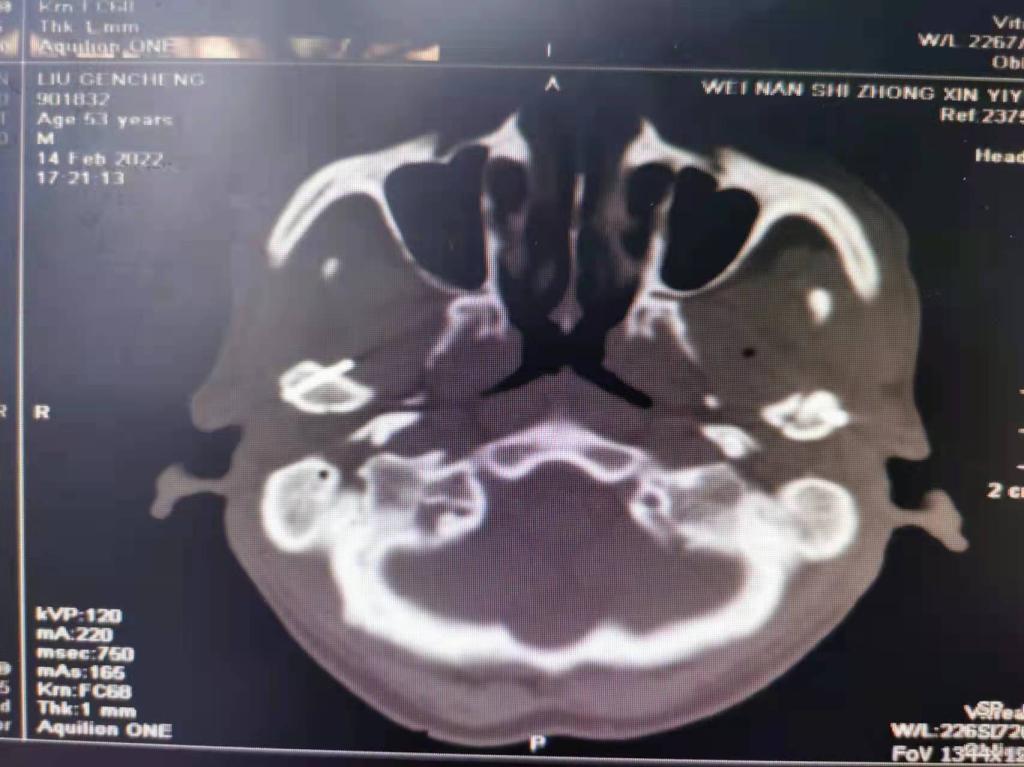

据了解,53岁的患者刘先生在1月25日当天走路不慎摔倒致下颌损伤,造成颏部软组织裂伤和张口困难,前往当地卫生院进行颏部裂伤清创缝合术。术后辗转到乐鱼在线登录入口口腔科门诊就诊,并进行颌面部CT检查提示为下颌颏部正中和双侧髁状突骨折,双侧下颌升支高度不一致,右侧较左侧变短1cm,张口重度困难,咬合关系错乱。刘先生因考虑在春节过后再入院治疗,于2月8日再次前来口腔科以“下颌骨骨折”收治人院。

口腔科主治医师蔺非非为患者入院后进行完善术前常规检查和颌间牵引恢复咬合关系。科主任李瑞春结合患者实际病情和检查结果认为,患者的髁突骨折在下颌骨骨折中所占比例较高,约为17.0%-36.3%。髁突骨折时,耳前区有明显的疼痛,局部肿胀、压痛。通过手指深入外耳道或在髁突部触诊,如张口时髁突运动消失,可能有骨折段移位。双侧低位骨折时,2个髁突均被翼外肌拉向前内方,双侧下颌支被拉向上方,可出现后牙早接触,前牙开秴。髁状突骨折易引起下颌后缩,张口困难,咬合关系错乱,关节强直等并发症。考虑患者系陈旧性骨折应尽早实施手术,避免骨折导致的张口困难、关节强直等并发症。因患者已经错过最佳治疗时期,决定尽快为患者进行手术治疗。

科主任李瑞春和主治医师蔺非非经过缜密的术前讨论和充分评估,手术在全身麻醉下进行,术中克服术野狭小操作不便困难,将下颌骨骨折完好对位,顺利地完成了"双侧髁状突和下颌颏部正中骨折切开复位内固定术"。术后检查患者面部对称,双侧下颌升支高度一致,咬合关系已恢复。